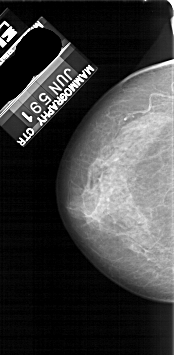

A_1118_1.LEFT_CC

LEFT_CC LINES 4966 PIXELS_PER_LINE 2431 BITS_PER_PIXEL 12 RESOLUTION 43.5 NON_OVERLAY

FILE: A_1118_1.RIGHT_CC.OVERLAY

TOTAL_ABNORMALITIES 1

ABNORMALITY 1

LESION_TYPE MASS SHAPE IRREGULAR MARGINS SPICULATED

ASSESSMENT 4

SUBTLETY 2

PATHOLOGY MALIGNANT

TOTAL_OUTLINES 2

BOUNDARY

CORE